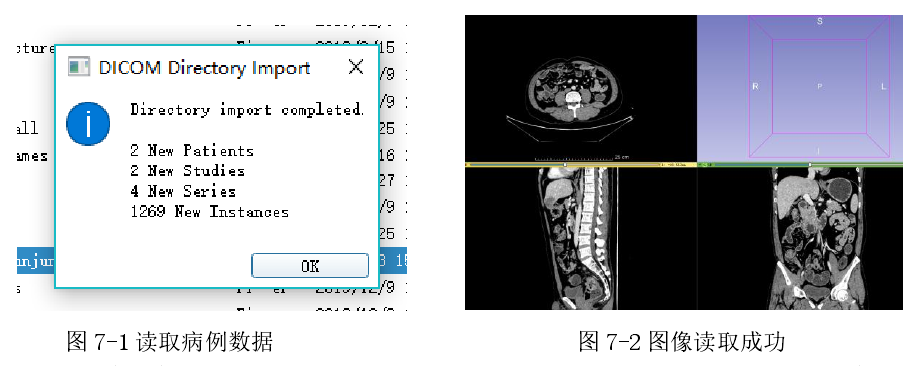

6.2.1 导入DICOM序列文件

如上图(图 7-1)所示,在读取 DICOM 文件后系统主界面上三个方向的切片视图中会生成对应 CT 序列。右上角为模型视图,图中视图的位置结构均可手动调节。